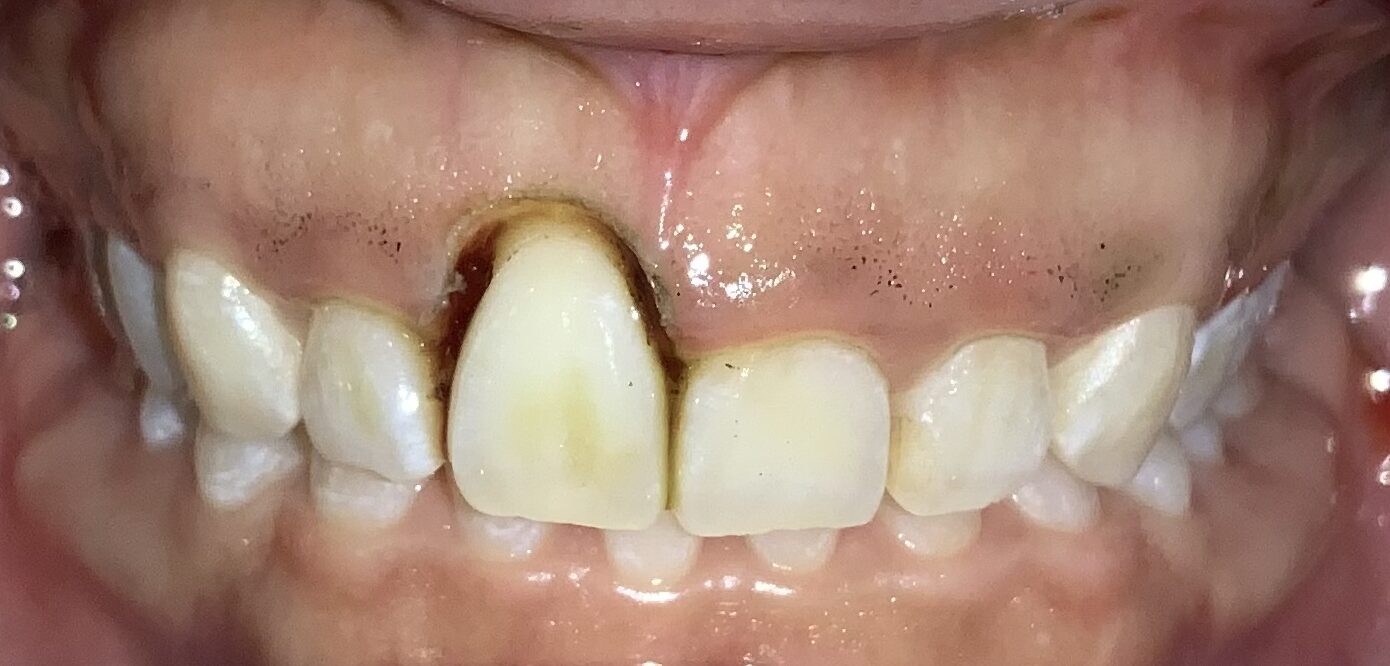

今回の患者様の治療前の状態です。

歯ぐきの長さに比較して、歯が少し小さいですね。歯ぐき自体は健康で綺麗なピンク色をしています。